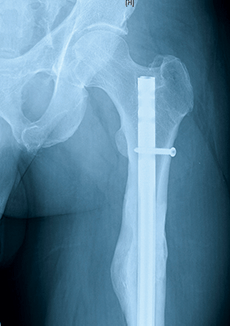

A 45-year-old man struck by a car sustained a closed left femoral shaft fracture. He was treated at a regional trauma center with intramedullary nailing. One year after injury, he presented to our trauma experts at NewYork- Presbyterian/Columbia with ongoing left thigh pain. Although X-rays suggested healing and the patient was told his fracture had healed, CT scan showed a nonunion.

On exam, the patient had a large soft tissue fluid collection on the left lateral thigh consistent with a Morel-Lavallée lesion. Once the nonunion was identified by CT, the surgical plan for exchange nailing was straightforward. However, the huge cystic soft tissue lesion was more challenging.

In surgery, an exchange nailing with reaming was performed, bringing the nail up 2mm in diameter. A huge fluid collection was seen, debrided, and sutured closed over a drain. Both the nonunion and the Morel-Lavallée lesions healed quickly after revision surgery. Postoperative X-ray at one year shows excellent bone healing. The patient has resumed his career as a construction contractor.